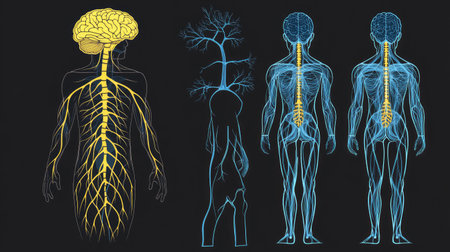

Illustrating the role of the central nervous system in processing sensory information and coordinating motor responses.

A captivating digital depiction of the human nervous system, highlighting the brain and spinal cord with glowing neural connections, perfect for educational materials.

Detailed anatomical illustration showing the human brain, spine, and nervous system with a focus on the intricate connections between them

An Electro stimulation digital illustration of human nervous system, highlighting brain and spinal cord with glowing nerve pathways